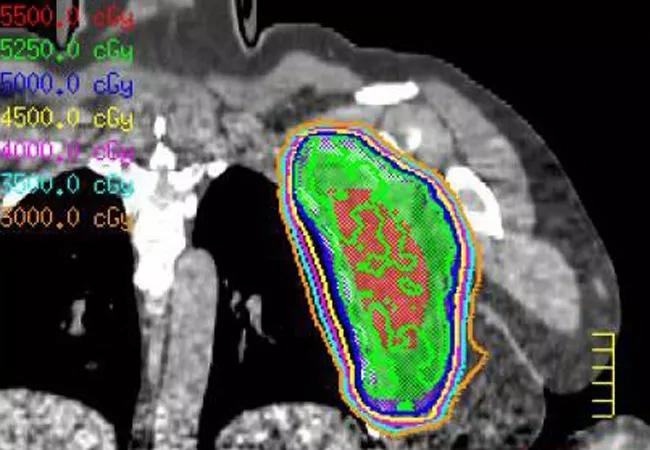

Soft-Tissue Sarcomas: Consider Radiation First, Surgery Second

Preop rad therapy can offer reduced treatment duration, improved long-term functioning

Why? Because some of the masses may be soft-tissue sarcomas, and sarcomas, particularly intermediate- and high-grade sarcomas, can be treated with preoperative radiation therapy followed by surgery, rather than surgery followed by postoperative radiation therapy. According to clinical trial data, this approach can improve long-term quality of life and overall functioning.

Preoperative radiation has not demonstrated an improvement in survival compared to postoperative radiation but instead shortens the duration of radiation therapy and offers the potential for improved long-term functioning by reducing fibrosis and joint stiffness, according to Dr. Shah.

Potential benefits of preoperative radiation, as compared to a postoperative approach, include shorter duration of treatment, lower total radiation dose, smaller area requiring radiation, reduction in long-term side effects, and improved overall long-term functioning.